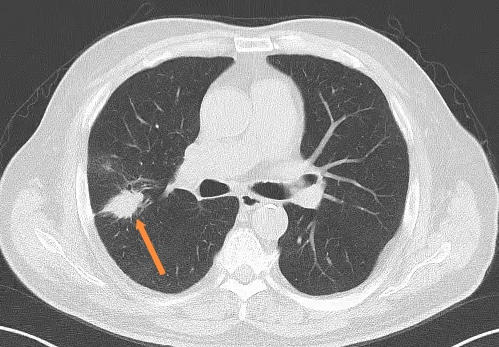

主要目的是排除乳房恶性肿瘤,乳腺DR(钼靶)可以发现以钙化为主的非肿块型乳腺癌,彩超对乳房结节检出率更高,各有优势。